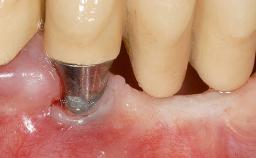

Early Implant Placement, Contour Augmentation, and Autologous Connective-Tissue Graft Using a Tunneling Technique to Replace an Upper Incisor with Generalized Gingival Recession

Variations in soft-tissue volume, evidenced either by an overabundance (Evian and coworkers 1993; Levine and McGuire1997; Dolt and Robbins 1997) or by a deficiency of soft or hard tissue can complicate implant-supported rehabilitations in the esthetic zone (Lorenzana 2008; Lorenzana and coworkers 2009). The present case illustrates the replacement of a failing upper left lateral incisor complicated by generalized severe gingival recession in the esthetic zone.

| Soft Tissue Contour and Volume | Significantly deficient |